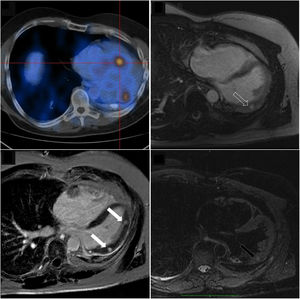

A 46-year-old male was referred to the cardio-oncology clinic for comprehensive cardiovascular assessment. He had a medical history of bronchial carcinoid, having undergone left pneumonectomy 20 years earlier, and was diagnosed with stage IV disease (bone and liver metastasis). A 68Ga-DOTATOC positron emission tomography (PET) scan in July 2019 was notable due to two foci of abnormally high radionuclide uptake at the left inferolateral aspect of the cardiac silhouette (Figure 1, upper left panel).

Right lower panel: Cardiac magnetic resonance imaging showing two rounded, well-defined intramyocardial high signal intensity lesions in T2-weighted sequences, at the medium and distal segments of the anterolateral wall (dark arrow). These two lesions showed isosignal intensity in T1-weighted images, and intense early (upper right panel, dashed arrow) and late (lower left panel, white arrows) gadolinium enhancement; Upper left panel: Positron emission tomography image shows increased 68Ga-DOTATOC uptake, further supporting the anatomic correspondence of these foci.

He had no cardiovascular symptoms. Clinical examination was unremarkable. The electrocardiogram showed sinus rhythm with no ST-T abnormalities. Transthoracic and transesophageal echocardiograms revealed no relevant structural or functional abnormality. Cardiac magnetic resonance imaging (MRI) showed two rounded, well-defined intramyocardial high signal intensity lesions in T2-weighted sequences, at the medium and distal segments of the anterolateral wall (Figure 1, right lower panel, dark arrow). These two lesions showed isosignal intensity in T1-weighted images, and intense early (Figure 1, right upper panel, dashed arrow) and late (Figure 1, left lower panel, white arrows) gadolinium enhancement. The anatomic correspondence between PET and cardiac MRI lesions led to diagnosis of cardiac metastasis of primary bronchogenic carcinoid.